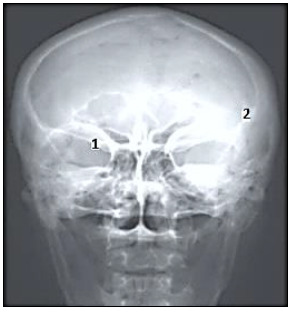

Com base na imagem radiológica apresentada, os números expostos referem-se, respectivamente, a quais estruturas anatômicas?